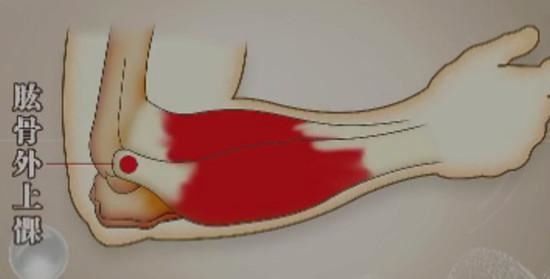

网球肘即肱骨外上髁炎或伸腕肌总腱肌腱炎,和高尔夫球肘(肱骨内上髁炎)、髌腱炎、跟腱炎等疾症一样,都是一种肌腱因遭受过度牵拉而引发的慢性肌腱病。网球肘的;诱因是伸腕肌肌腱的长期过度使用,使其遭受累积性的、难以自我修复的损伤,使肌腱出现纤维化、钙化、无菌性炎性、疼痛等症状。更深入地讲,绝大多数肌腱病的诱因都是肌肉的延展性差和力量不足(尤其是离心收缩力量的不足)。

网球肘引发的肱骨外上髁(肘关节外侧的、位于上臂远端的部分)疼痛,往往都是逐步发展的慢性疼痛,这种疼痛起初只在肘关节大量运动后出现,如果这类运动比较频繁,疼痛感会越来越强烈,甚至在日常生活中的握手、提物、拧毛巾、转门把手等动作中也会出现显著的疼痛。这种疼痛在休息时会有减轻,在肘关节伸展和放松的情况下可能会消失。

1、查体。用手指按压肱骨外上髁(上臂、末端外侧区域),会有比较明确的、敏锐的疼痛;在肘伸直、握拳、屈腕状态下前臂旋前,会在该区域出现显著疼痛;前臂旋前的情况下负重旋后,也会出现疼痛。中期和早期的患者,不会在肱骨外上髁处出现肿胀等异常表现,长期的患者可能会出现伸腕肌的萎缩。2、影像学检查。X光一般没有异常(比较严重者可能会有钙化点);超声波检查可能会发现肌腱纤维化、钙化等表现;MRI(核磁共振)检查可以较好地观察到软组织和骨骼病变,但对初期的病变仍难以探查。3、鉴别诊断。如有外伤史,或者是短期内出现的急性疼痛,亦或同时存在神经病变的症状(感觉缺失、烧灼痛等),应通过影像学检查、查体、病史询问等方式与骨折、韧带损伤、肌腱断裂、神经病变等疾病进行鉴别诊,。断。